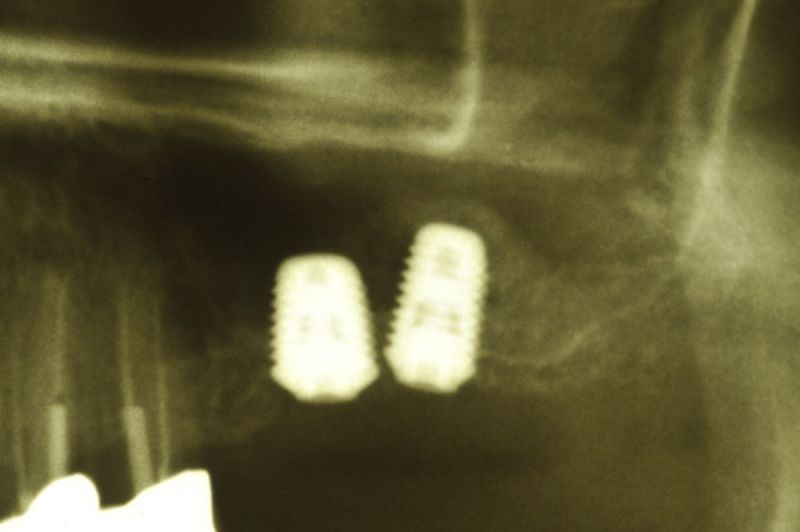

Aus parodontalen Gründen mussten bei der Patientin im Oberkieferseitenzahnbereich mehrere Zähne entfernt werden. Auf der rechten Seite wurden bereits zwei Implantate, mit einem externen Sinuslift verbunden, gesetzt.

Heute wurden die Zähne 15 und 17 entfernt. An Zahn 15 erkennt man ein großes Granulom, im Sinne einer chronischen Entzündung, um die Wurzelspitze herum. Dieses Granulom hat der Patientin keinerlei Beschwerden verursacht. Der Zahn hätte aber so nicht gehalten oder versorgt werden können, weil dieses Granulom die Tendenz hat sich weiter zu vergrößern und dabei Knochen einzuschmelzen, der wiederum für den Halt der Zähne benötigt wird.